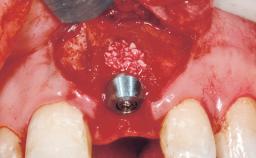

Placement Protocol Immediate implant placement

Socket Morphology Single-root socket

Socket Integrity Sufficient, with intact bone walls

Bone Volume Sufficient, with intact walls